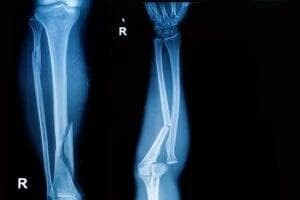

Broken bones (fractures) vary in severity and type. For instance, a small hairline fracture might heal with minimal intervention, while a compound fracture can necessitate multiple surgeries. Commonly, these injuries involve:

- Simple (Closed) Fracture: The bone cracks but does not pierce the skin.

- Compound (Open) Fracture: Bone fragments break through the skin, increasing infection risk.

- Comminuted Fracture: The bone shatters into multiple pieces, often requiring pins or plates to realign.

According to the American Academy of Orthopaedic Surgeons (AAOS), fracture treatment can include setting the bone in a cast, insertion of surgical hardware, or traction, depending on complexity. Even well-managed breaks may lead to lingering pain or reduced mobility, particularly if the injury affects load-bearing bones like the femur or spine. These limitations might interfere with work and everyday routines, highlighting the importance of full and fair compensation for associated expenses.